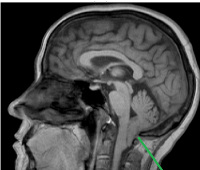

Наряду с клиническим обследованием важное значение в диагностике имеет выполнение рентгенографии черепа и рентгенографии шейного отдела позвоночника. С целью визуализации мягкотканных структур краниовертебрального перехода назначают МРТ головного мозга и МРТ позвоночника в шейном отделе. Исследование выполняется в режимах Т1 и Т2, в сагитальной и аксиальной проекциях. По показаниям проводят МРТ сосудов головного мозга. При невозможности МРТ-обследования, а также для более точной визуализации костных образований краниовертебральной зоны, выполняют КТ позвоночника и КТ головного мозга.